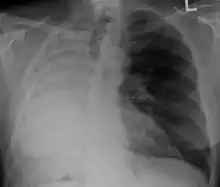

After a pneumonectomy is performed, changes in the thoracic cavity occur to compensate for the altered anatomy. The remaining lung hyperinflates as well as shifting over along with the heart towards the now empty space. This space is full of air initially after surgery, but then it is absorbed, and fluid eventually takes its place.[9] The fluid which fills the residual space in the chest cavity slowly gelatinizes into a proteinaceous material, and the chest scaffold collapses slightly.

X-ray of a person who has had their right lung removed. Note how fluid has replaced the lung